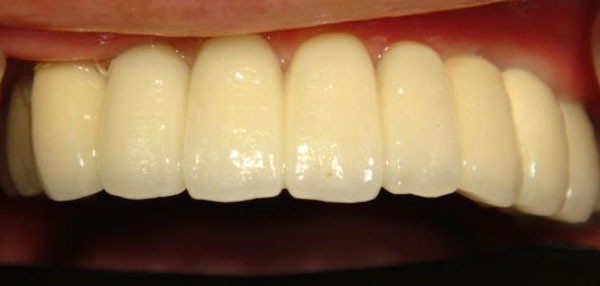

全口重建

全口無牙的並做重建有幾個要點必須注意!

全口無牙患者種植,猶同是搬新家,再蓋一間毛胚屋要開始做裝潢設計......。於是良好的設計跟裝潢材料的選用,就決定了這個裝潢可以用多久。